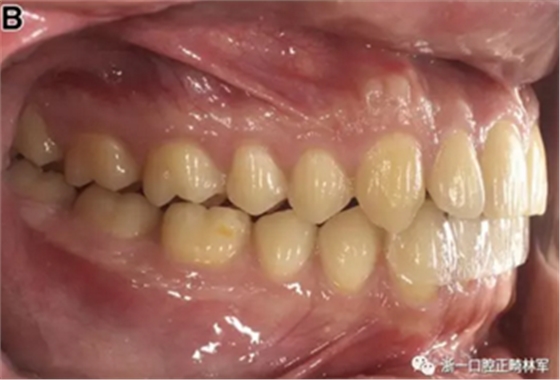

患者的上頜骨和下頜骨研究模型在最大牙尖交錯(cuò)位時(shí)確定和數(shù)字化(圖2,A),作為咬合指導(dǎo)(咬合指導(dǎo))。該數(shù)字化咬合指導(dǎo)在齦緣周圍進(jìn)行數(shù)字化修剪,以便在CBCT掃描上可以更好得可視化(圖2,B)。

圖2. A,咬合時(shí)對象研究模型的右側(cè)舌側(cè)視圖掃描將作為未來指導(dǎo);該指導(dǎo)稍后用于將懸浮的下頜骨配對到修剪的上頜骨;B,左側(cè)舌側(cè)視圖的數(shù)字化修整牙合引導(dǎo)。